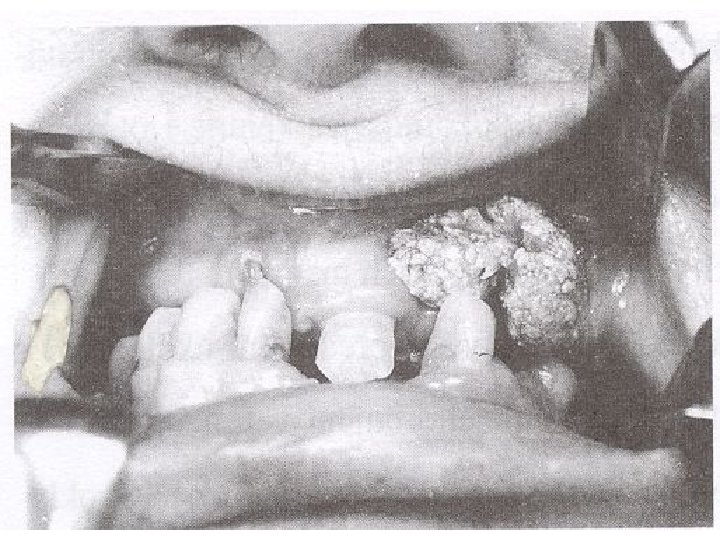

Leukoplakie – doprovázena benigním zvětšením dásně

Kaposiho sarkom

Metastázní ložiska na jazyku

Maligní karcinom jazyka možný jen u kuřáka

Papilom jazyka

Karcinom horního patra

Gingiva překrývající korunky zubů

Maligní nádor mandibuly